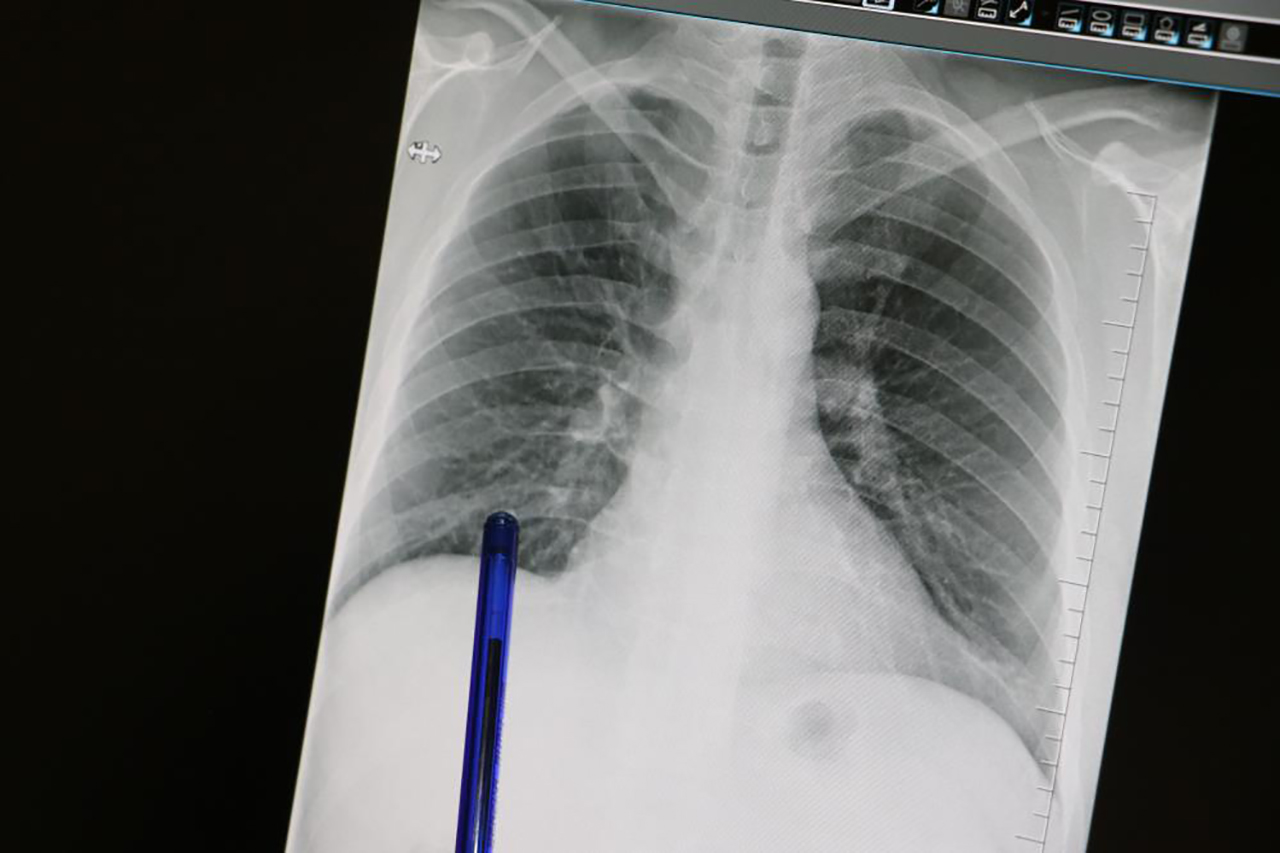

Basit Öksürük Bile Akciğer Kanserinin İlk İşareti Olabilir

Kasım ayı, Türkiye'de akciğer kanserine dikkat çekmek ve erken tanının önemini vurgulamak amacıyla ‘Akciğer Kanseri Farkındalık Ayı' olarak kabul ediliyor. Akciğer kanseri ise akciğer dokusundaki hücrelerin kontrolsüz çoğalmasıyla oluşan ve diğer organlara yayılabilen ciddi bir hastalık olarak biliniyor. Genellikle erken evrelerde belirti vermediği için geç fark ediliyor ve bu durumda tedavi şansını azaltıyor. En önemli risk faktörü sigara kullanımı olsa da, sigara içmeyen kişilerde de bu hastalık görülebiliyor. Pasif içicilik, hava kirliliği, genetik yatkınlık ve bazı kimyasal maddelere uzun süreli temas ileri yaşta akciğer kanseri riskini artıran diğer etkenler arasında bulunuyor. Konuya ilişkin açıklamalarda bulunan Medicana Sivas Hastanesi Göğüs Hastalıkları Uzmanı Dr. Büşra Yayla Yerlikaya, öksürük ve balgam çıkarma gibi basit görünen semptomların kanserin belirtisi olabileceğini söyleyerek, "Bu hastalık, hem dünyada hem de ülkemizde kansere bağlı ölümlerin en sık nedenidir. Ne yazık ki genellikle erken evrede belirti vermediği için geç tanı alabilmekte ve bu da tedavi şansının azalmasına sebep olabilmektedir" dedi.

Özellikle sigara içen bireyde öksürük gibi belirtiler varsa bir uzman tarafından değerlendirilmesi gerektiğini belirten, "Akciğer kanserinin en sık belirtileri ise uzun süren öksürük, balgamda kan, nefes darlığı, kilo kaybı ve göğüs ağrısıdır. Özellikle sigara içen birinde yeni başlayan ya da karakteri değişen öksürük varsa mutlaka bir göğüs hastalıkları uzmanı tarafından değerlendirilmelidir. Erken tanı her kanser türünde olduğu gibi akciğer kanserinde de hayat kurtarır. 50 yaş üzeri ve uzun süre özellikle 20 paket yıl ve daha fazla sigara içmiş kişilerde düşük doz tomografi ile tarama yapılması, hastalığın erken evrede erken tanı sağlar ve tedavi şansını ciddi şekilde artırır. Sigarayı bırakmak her yaşta faydalıdır. Bıraktıktan sonraki on yıl içinde akciğer kanseri riski büyük oranda azalır. Çalışmalar 10 yıl sonra yüzde 50, 15 yıl sonra ise yüzde 90'a kadar akciğer kanseri riskinin azaldığını göstermiştir. Sigara içen bireylerde sabahları balgam ve öksürükler mevcut oluyor. Bu durumlarda balgamın karakter değiştirmesi ve artması önemli bir belirti olabiliyor" diye konuştu.